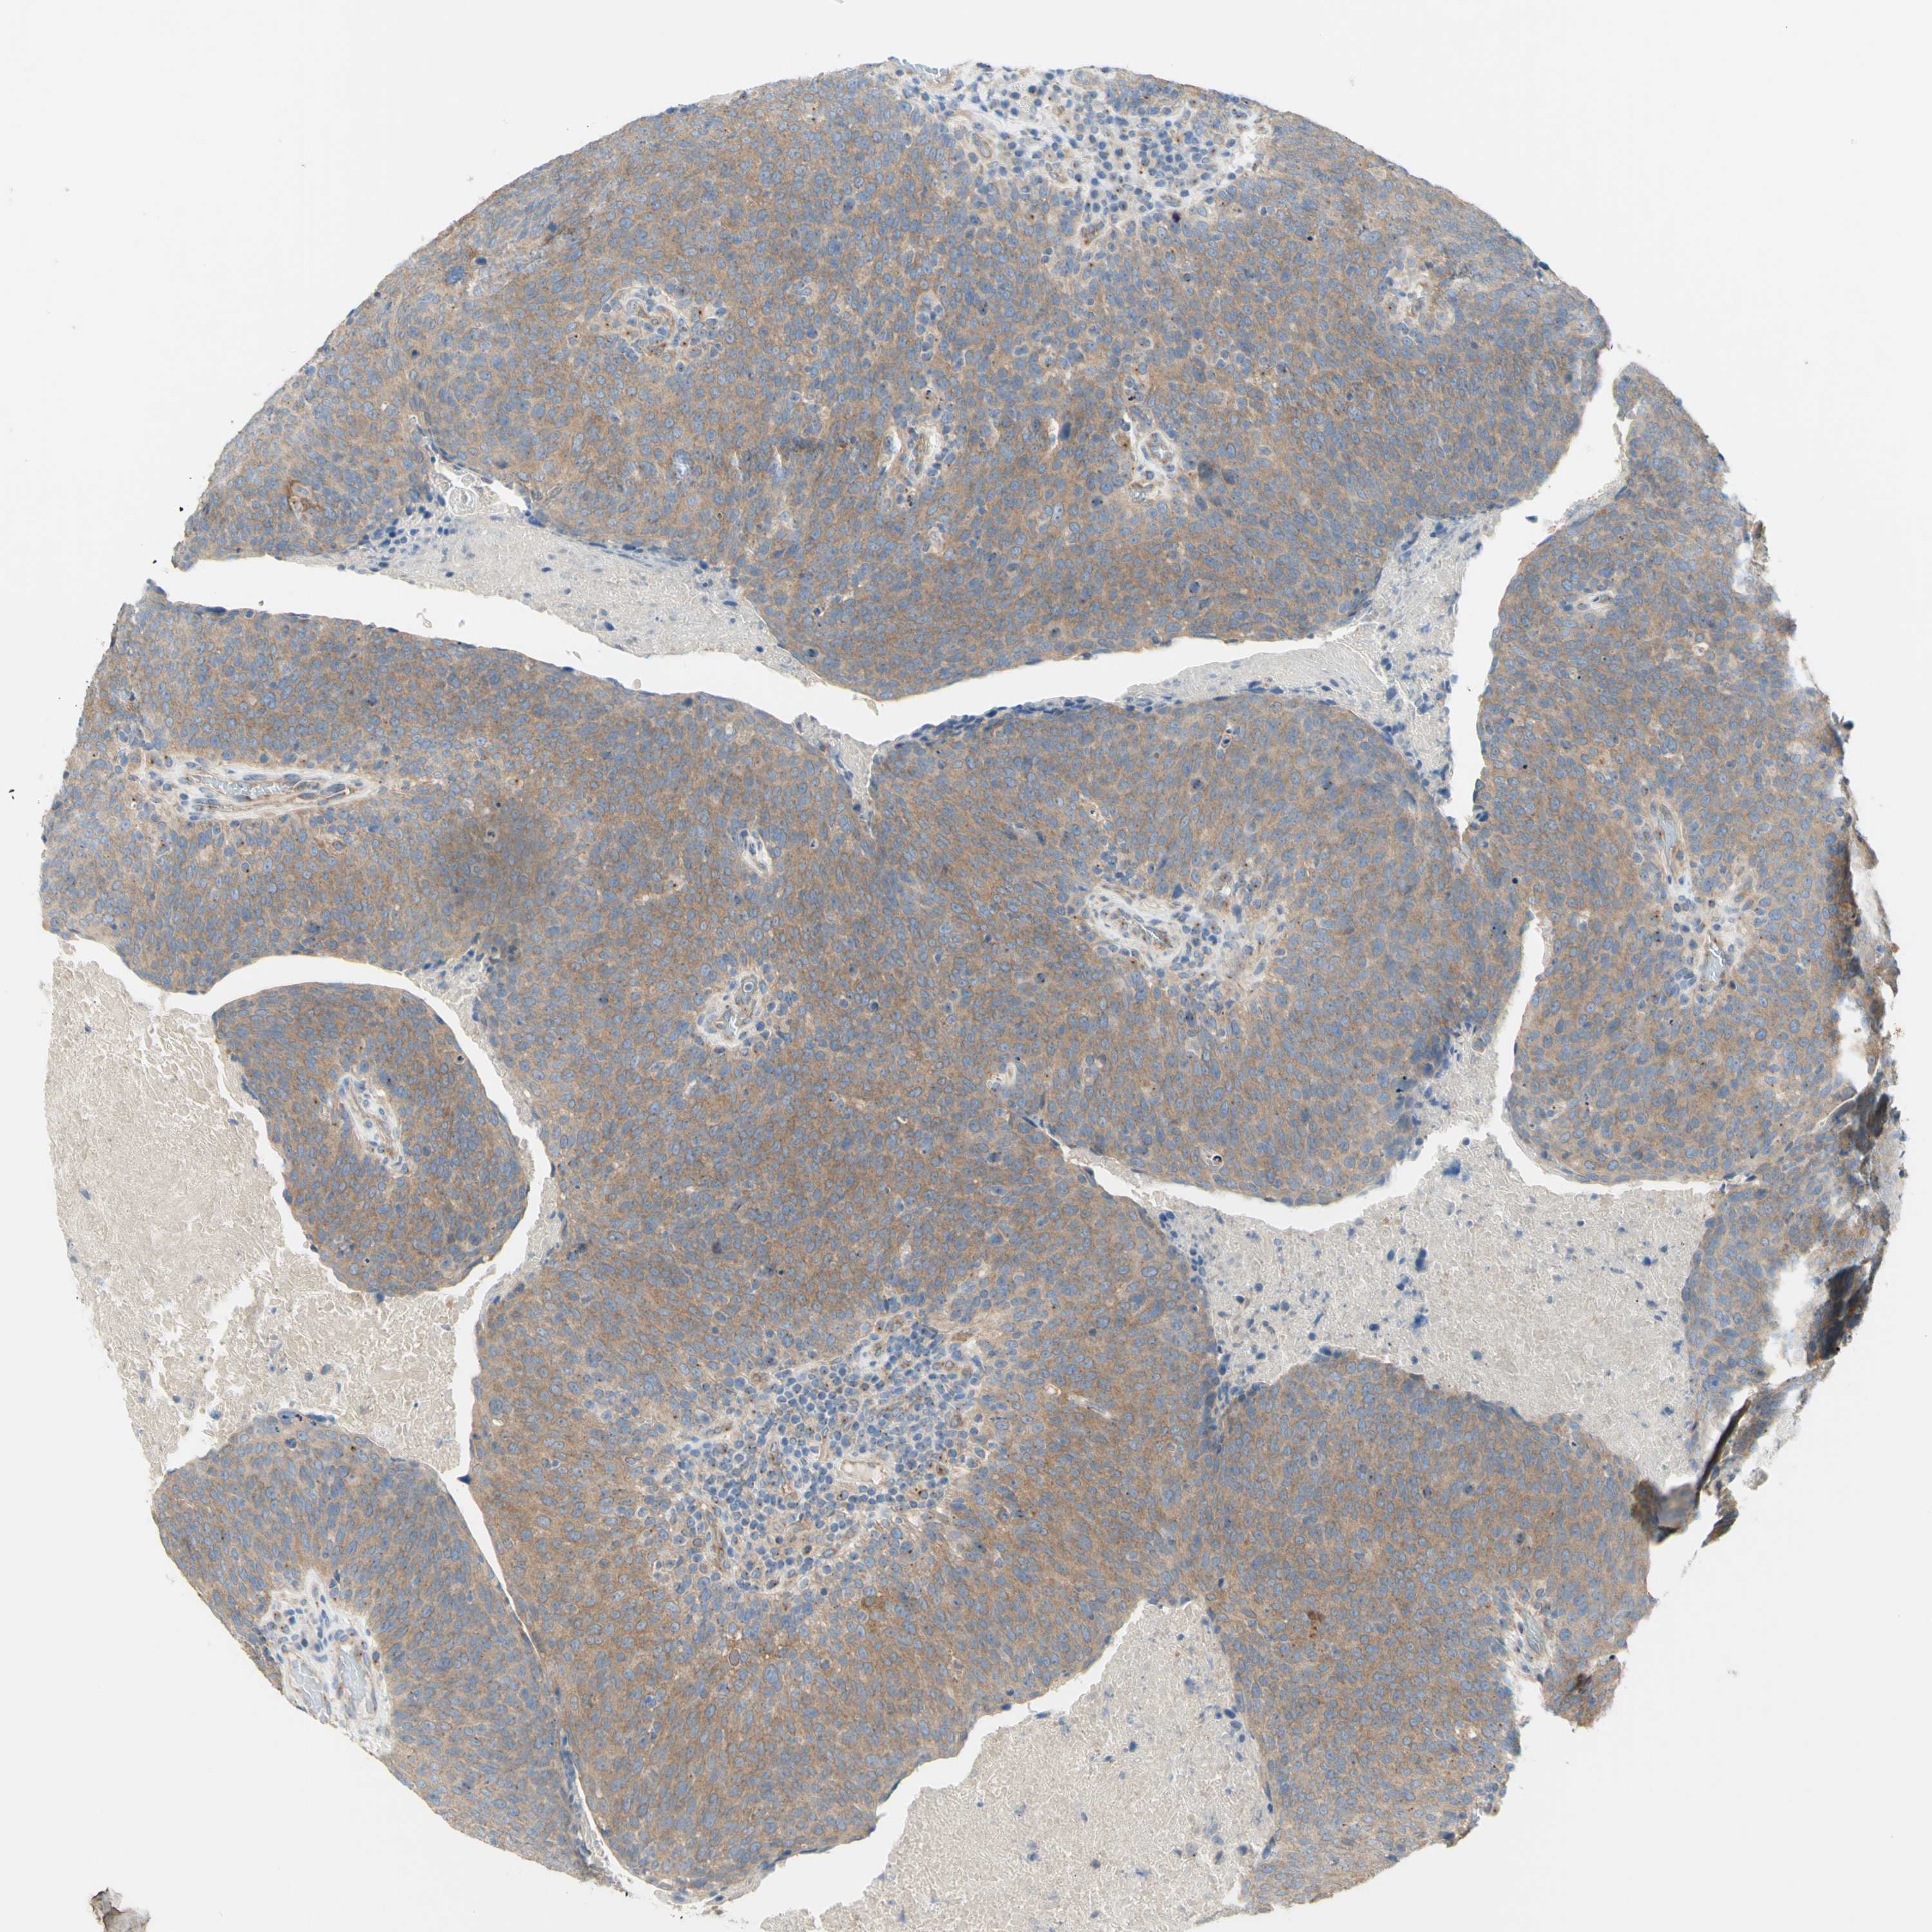

HEAD AND NECK CANCER - Protein expressioni

A mouse-over function shows sample information and annotation data. Click on an image to view it in a full screen mode. Samples can be filtered based on level of antibody staining by selecting one or several of the following categories: high, medium, low and not detected. The assay and annotation is described here.

Antibody stainingi

Antibody staining in the annotated cell types in the current human tissue is reported as not detected, low, medium, or high, based on conventional immunohistochemistry profiling in selected tissues. This score is based on the combination of the staining intensity and fraction of stained cells.

Each image is clickable and will lead to virtual microscopy that enables deeper exploration of all samples and also displays staining intensity scores, fraction scores and subcellular localization as well as patient and tissue information for each sample.

Antibody HPA003742

Antibody CAB010443

Staining

High

Medium

Low

Not detected

Intensity

Strong

Moderate

Weak

Negative

Quantity

>75%

75%-25%

<25%

None

Location

Nuclear

Cytoplasmic/membranous

Cytoplasmic/membranous,nuclear

Squamous cell carcinoma, NOS

Squamous cell carcinoma, metastatic, NOS

Adenocarcinoma, NOS

Adenoma, NOS